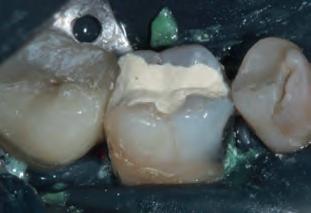

Periapical X-ray confirmed the findings of the clinical examination and root caries was also detected in the distal root of tooth #46, which answered positively to the sensitivity test (Fig.1-2).

The treatment plan began with a focus on returning the patient to adequate periodontal health. In a subsequent session, with improved condition of the periodontium, the restoration of tooth #46 was performed. Under block anesthesia of right inferior alveolar nerve and rubber dam isolation, the amalgam restoration was completely removed and access to the caries cavity obtained (Fig. 3-5). Despite the proximity to the pulp tissue, no exposure occurred, and the class II cavity was fully restored with Biodentine™ (Fig. 6-8).

Fig. 1: Initial clinical situation.

Fig. 4: Septomatrix in position.

Fig. 2: Initial X-ray.

Fig. 5: Cavity deep.

Fig. 3: Class II cavity prepared.

Fig. 6: Biodentine™ applied in a Bio Bulk-Fill approach.